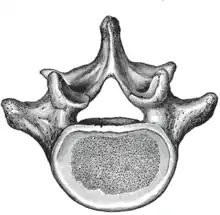

A typical lumbar vertebra

The adjacent figure depicts the general characteristics of the first through fourth lumbar vertebrae. The fifth vertebra contains certain peculiarities, which are detailed below.

As with other vertebrae, each lumbar vertebra consists of a vertebral body and a vertebral arch. The vertebral arch, consisting of a pair of pedicles and a pair of laminae, encloses the vertebral foramen (opening) and supports seven processes.

Body

The vertebral body of each lumbar vertebra is kidney shaped, wider from side to side than from front to back, and a little thicker in front than in back. It is flattened or slightly concave above and below, concave behind, and deeply constricted in front and at the sides.[1]

Arch

The vertebral foramen within the arch is triangular, larger than the thoracic vertebrae, but smaller than in the cervical vertebrae.[1]

Processes

The spinous process is thick, broad, and somewhat quadrilateral; it projects backward and ends in a rough, uneven border, thickest below where it is occasionally notched.[1]

The superior and inferior articular processes are well-defined, projecting respectively upward and downward from the junctions of pedicles and laminae. The facets on the superior processes are concave, and look backward and medialward; those on the inferior are convex, and are directed forward and lateralward. The former are wider apart than the latter since in the articulated column, the inferior articular processes are embraced by the superior processes of the subjacent vertebra.[1]

The transverse processes are long and slender. They are horizontal in the upper three lumbar vertebrae and incline a little upward in the lower two. In the upper three vertebrae they arise from the junctions of the pedicles and laminae, but in the lower two they are set farther forward and spring from the pedicles and posterior parts of the vertebral bodies. They are situated in front of the articular processes instead of behind them as in the thoracic vertebrae, and are homologous with the ribs.[1]